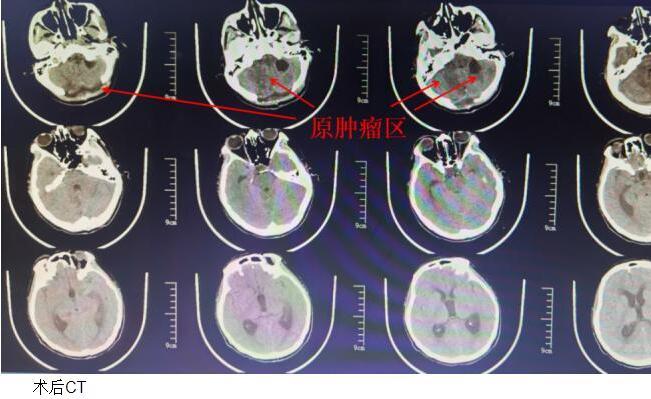

2024年2月2日,在松北院区麻醉科和手术室的通力配合下,赵振环主任团队为患者实施了后正中入路肿瘤切除+后颅窝减压手术,按照预定方案成功将患者延髓背侧肿瘤和右侧小脑的三个肿瘤完整切除。术后患者意识清楚,四肢活动自如,出现一过性口齿不清和吞咽不良,三天后逐渐好转,术后14天出院时双眼视力及视野均较术前有明显改善,说话及吞咽功能已完全恢复,目前在家休息中,准备近日来院复查。术后病理显示:血管母细胞瘤。